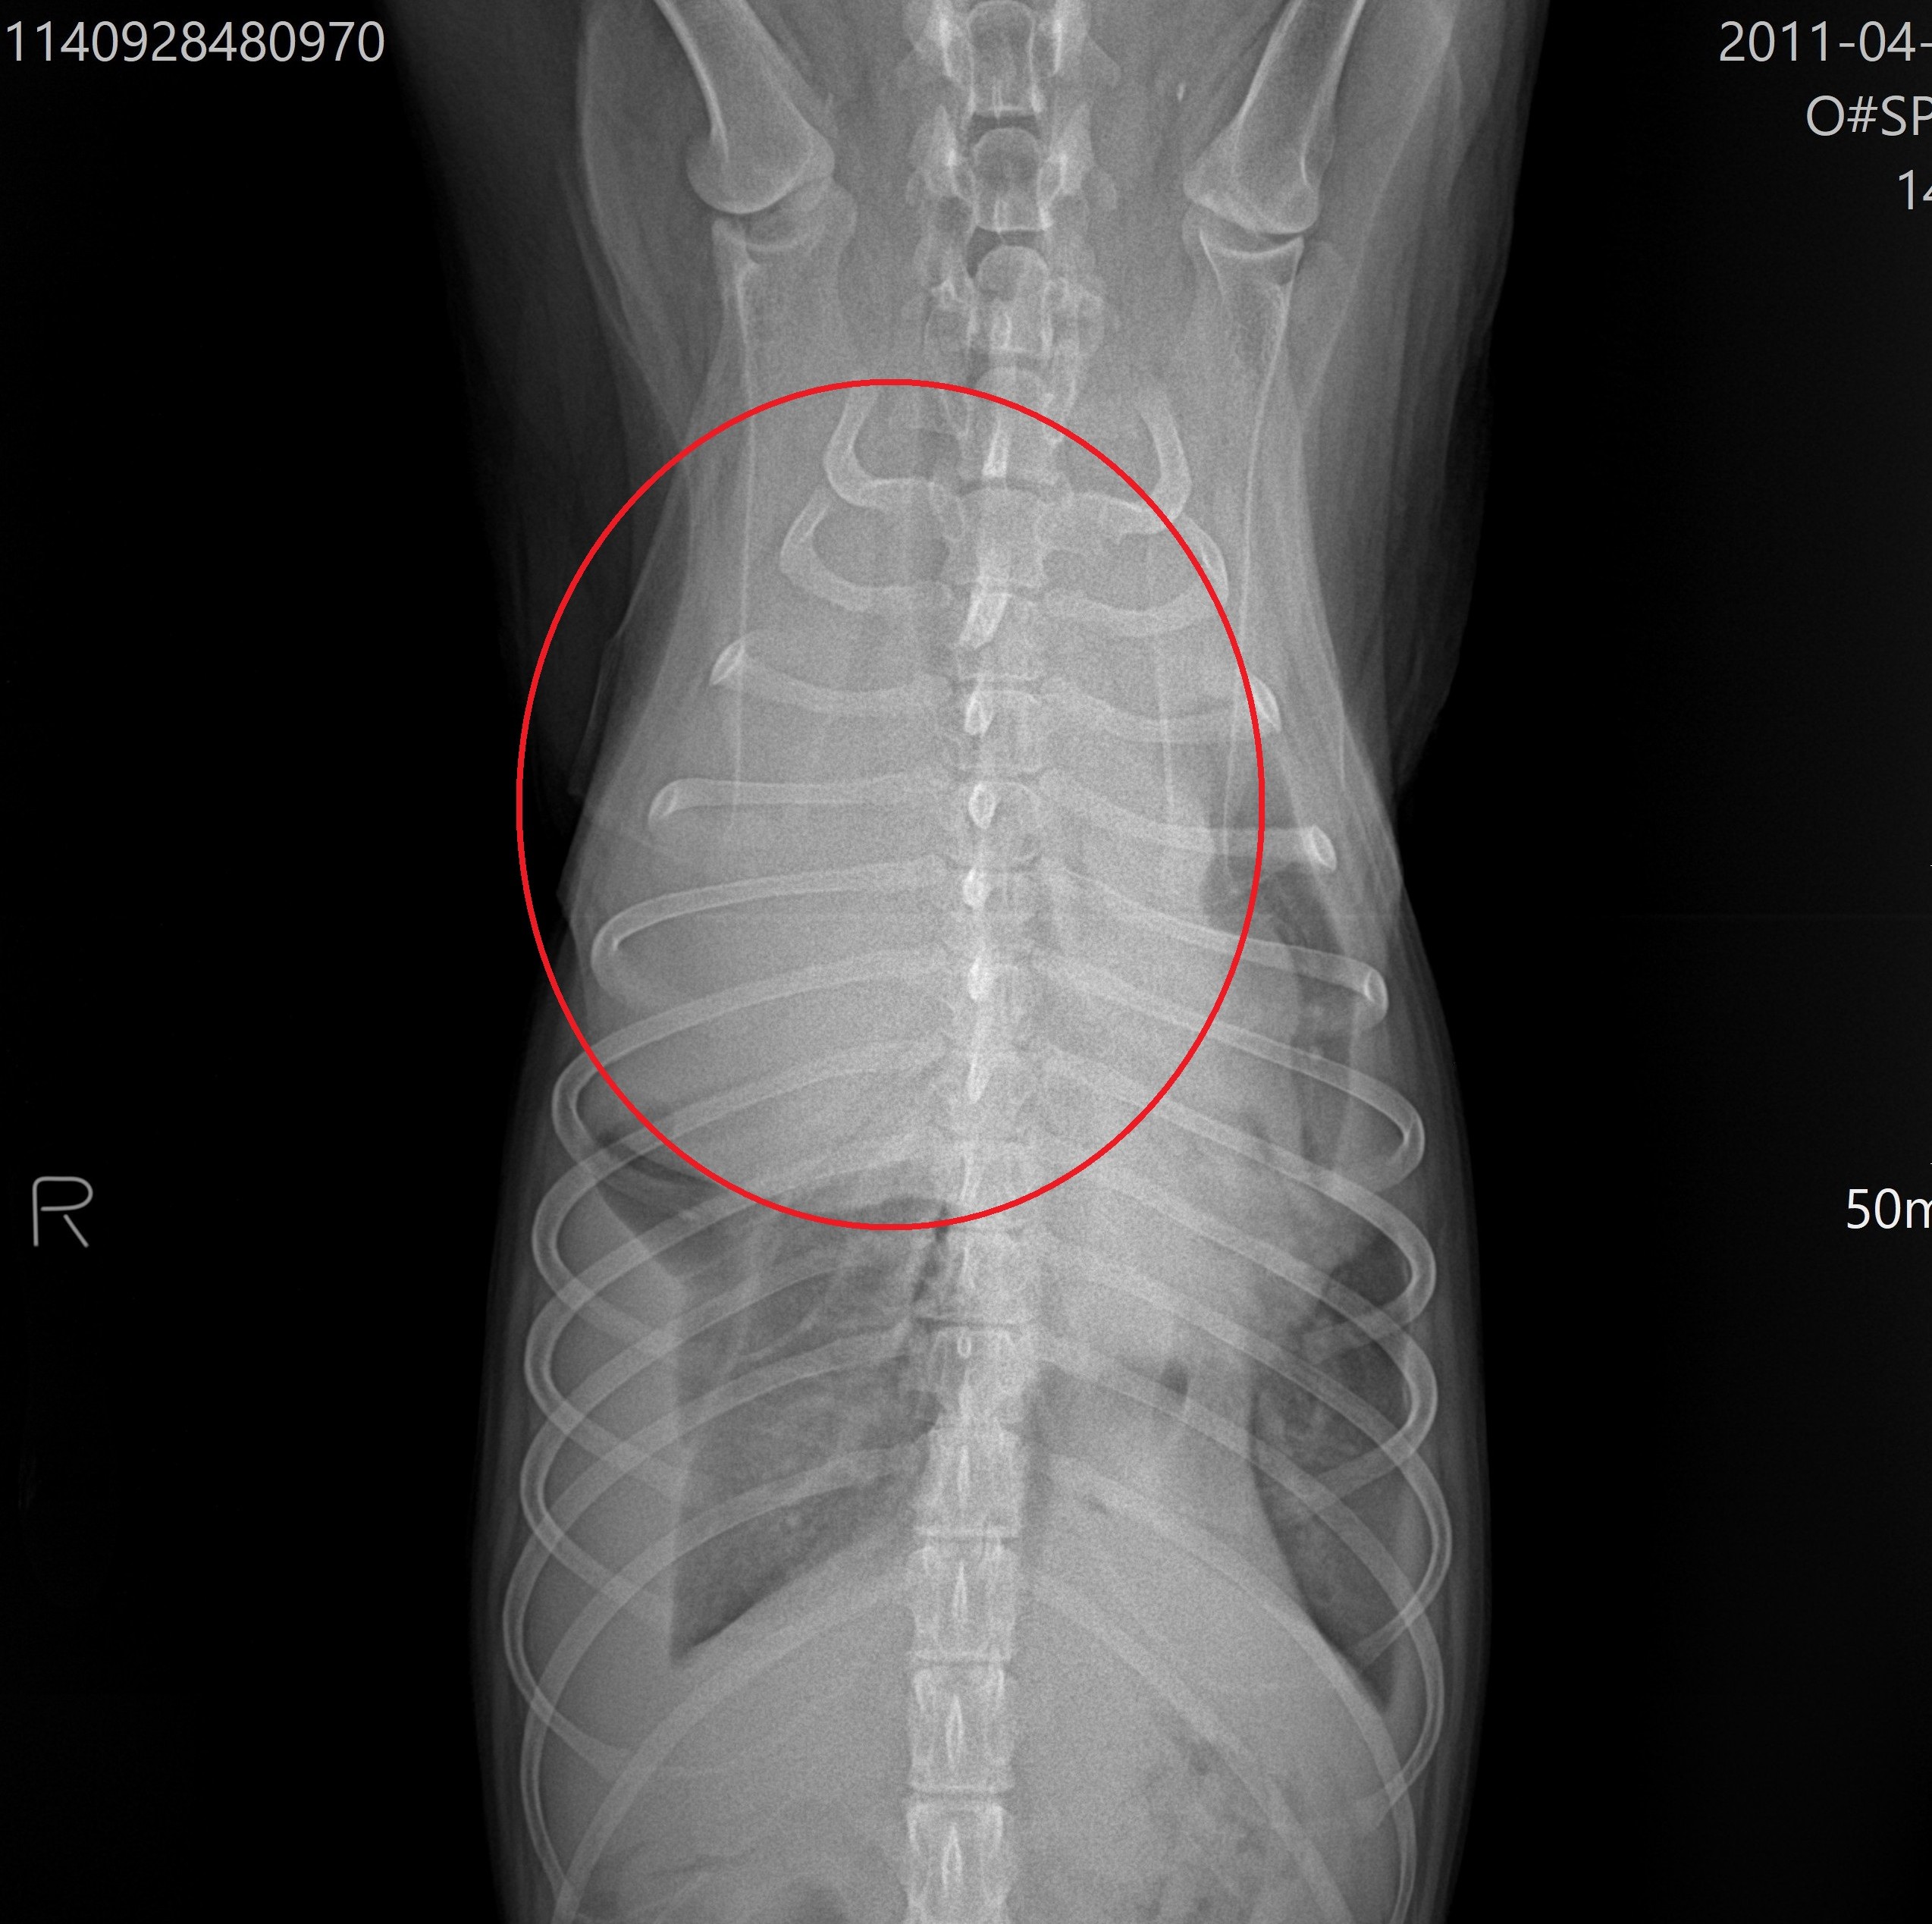

胸部レントゲン検査(腫瘤を赤丸で表示)

より詳しい評価が必要と判断し、沼津市の宮田動物病院にてCT検査をお願いしました。迅速に対応していただき、すぐにCT撮影を行っていただきました。

画像中の黒矢印で示した黄色の部分が、前胸部に認められた腫瘤です。

CT検査では、

- 前胸部腫瘤の大きさ

- 腫瘤に入り込む血管の走行

- 周囲臓器との位置関係

について、宮田先生からリアルタイムで非常に詳しく説明していただきました。